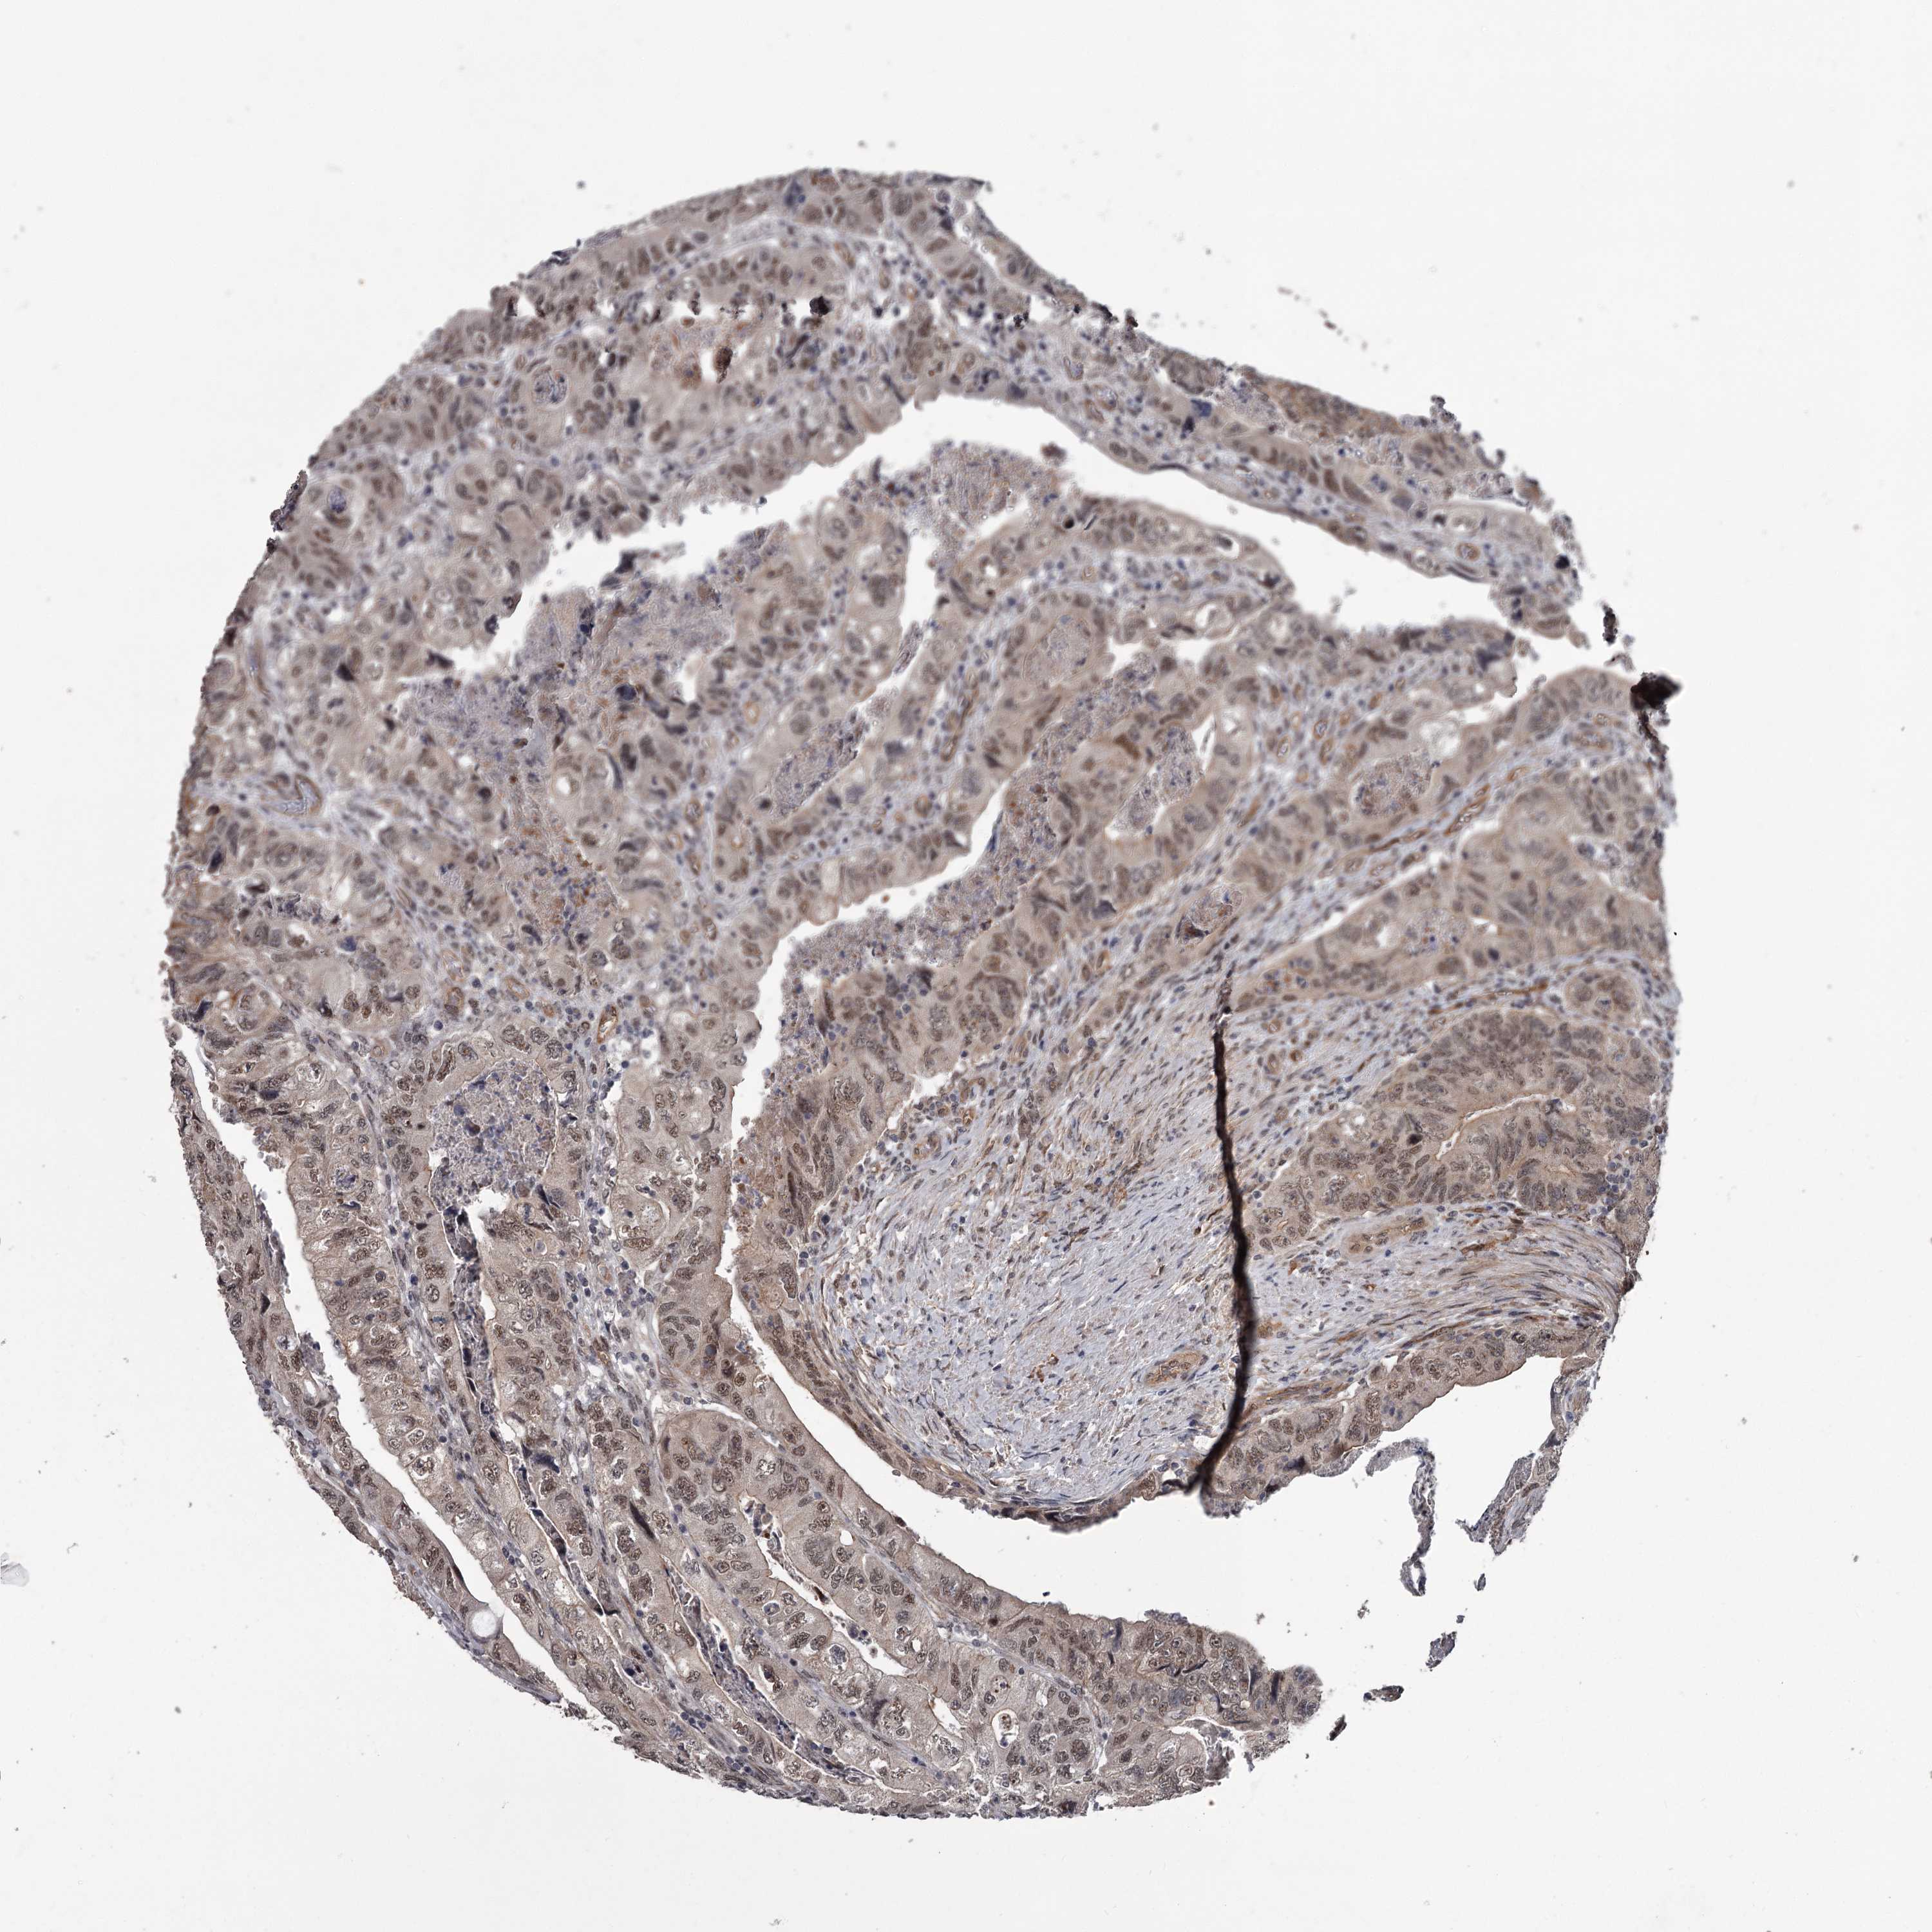

Colorectal cancer

Colon adenocarcinoma

Rectum adenocarcinoma